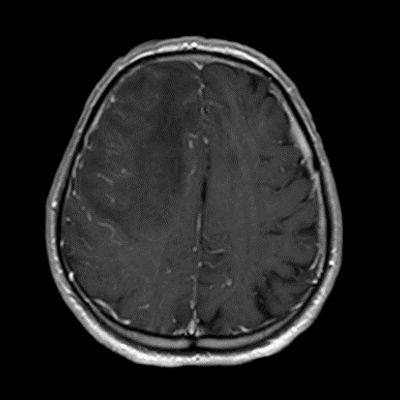

- D) Kontrastlı T1A sekansta hafif leptomeningeal boyanma (sarı ok).